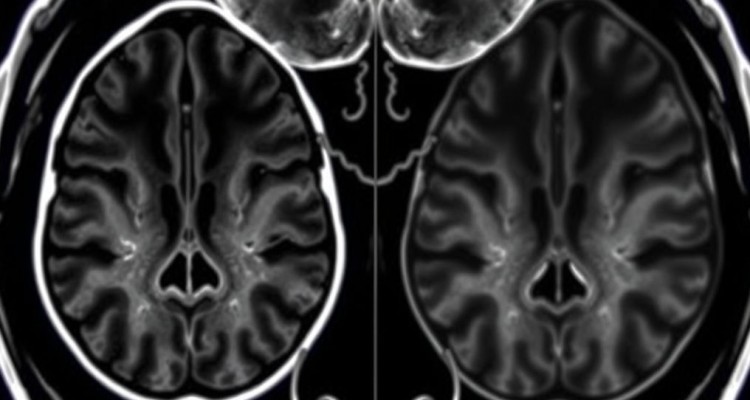

Врач оценивает высоту и структуру дисков, ширину спинномозгового канала, состояние связок, костные разрастания, сигнал от вещества спинного мозга и корешков. Также видно сирингомиелию, миелит, рассеянный склероз, последствия компрессии при стенозе. Снимки послойные, с шагом в миллиметры. Это как разрезать батон на тонкие ломти и рассмотреть каждый.

Чем МРТ лучше рентгена и КТ

В заключении врач описывает уровни позвоночника, состояние канала, дисков, корешков, субарахноидального пространства и вещества спинного мозга. Пример. «Грыжа L5–S1 вправо 7 мм с компрессией корешка S1» — это объясняет боль по задней поверхности бедра и стопы, а также слабость сгибания. Другой пример. «Очаги демиелинизации в шейном отделе» — повод для консультации невролога по поводу рассеянного склероза. Еще пример. «Посттравматический миеломаляция на уровне Th8» — говорит о повреждении спинного мозга после травмы.